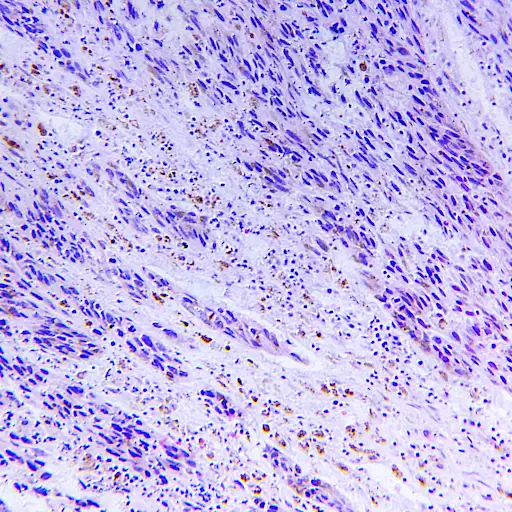

“分期是我们谈论黑色素瘤扩散的一种方式,”Fathi博士说。分期是由几个因素决定的,但最主要的是肿瘤的生长程度和是否转移。“第一阶段到第三阶段取决于皮肤癌在显微镜下的样子。他说:“我们寻找一些特征,比如癌细胞穿透了多少毫米深,显微镜下是否有溃疡,是否有大量细胞正在分裂。”在第四阶段,癌症已经发展到身体的其他部位、淋巴结或器官。